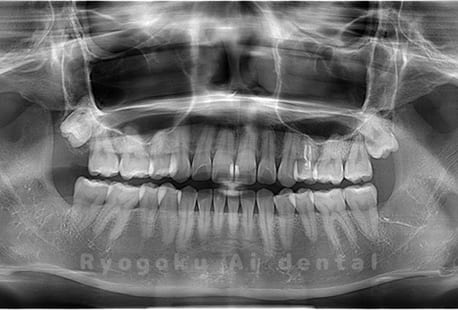

Case04

- 原因

- 上顎の親知らず、下顎の水平埋伏の親知らず

- 治療内容

- 上顎の親知らず、下顎の水平埋伏の親知らずを抜歯したケースです。

<リスク・副作用>

手術後は痛み、腫れ、痺れなどの副作用が生じる場合があります。